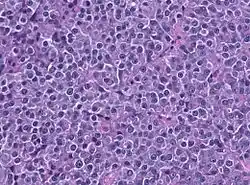

Prolactinoom

Een prolactinoom is een goedaardig gezwel in de hypofyse. Het is de meest voorkomende vorm van een hormoonproducerende hypofysetumor. Het produceert prolactine, het hormoon dat de melkproductie bij zwangere en zogende vrouwen stimuleert.